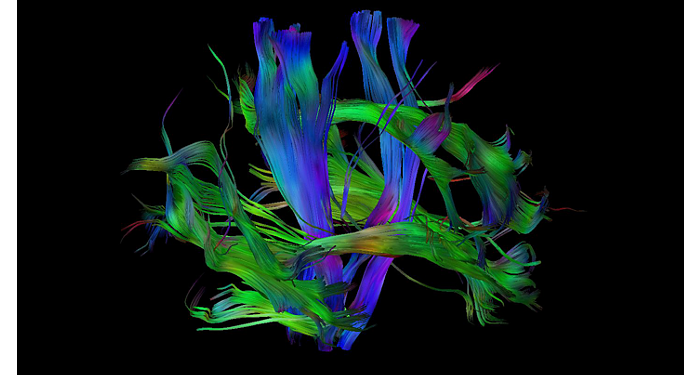

70% of radiologists consider neuro indications to be challenging, mostly due to a lack of appropriate imaging and visualization techniques¹. Philips aims to provide the best possible diagnostic clarity and treatment guidance for all patients with neurological disorders. By leveraging our dStream digital platform, this year, we are introducing, a set of novel imaging and visualization strategies. These may empower you to resolve complex neuro questions with more certainty, as well as unlock new neuro territories in advanced Neurofunctional applications. This is a key step towards elevating neuro diagnostics and ultimately touching more lives with MR imaging. ¹ TMTG Market Survey 2016

New neuro applications